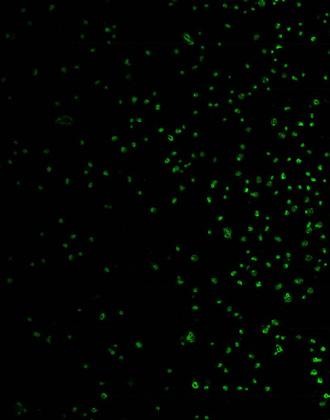

Afbeelding van de ronde vorm van de Borrelia-bacterie.*

In de tweede experimentenreeks onderzochten we diezelfde combinatie van micronutriënten en hetzelfde antibioticum, op hun effectiviteit bij het doden van de ronde vorm van de Borrelia bacteriën. Zoals te zien is op de grafiek, is het antibioticum op dit moment nauwelijks nog effectief en het percentage van actieve bacteriën blijft onder antibiotische behandeling net zo hoog (rode lijn). Daarentegen wordt het percentage van actieve bacteriën, door het gebruik van micronutriënten, met de helft verlaagd (zwarte lijn).

Afbeelding 2

De synergie van micronutriënten is effectiever dan het antibioticum Doxycyclin, in het doden van de ronde vorm van Borrelia- bacteriën.